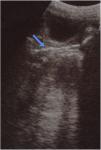

There was no history of trauma, sexual abuse, soreness, urinary or rectal complaints. The symptoms did not respond to hygiene measures and appropriate antibiotic therapy. The physical examination revealed no abdominal tenderness and normal external genitalia, with no lesions or active discharge. However, there was a bloody and foul-smelling discharge on the sanitary pad. A pelvic ultrasound scan (Fig. 1) and a pelvic radiograph (Fig. 2) revealed the presence of a foreign body measuring 40×10mm. The patient underwent vaginoscopy under anaesthesia for removal of a hair clip.